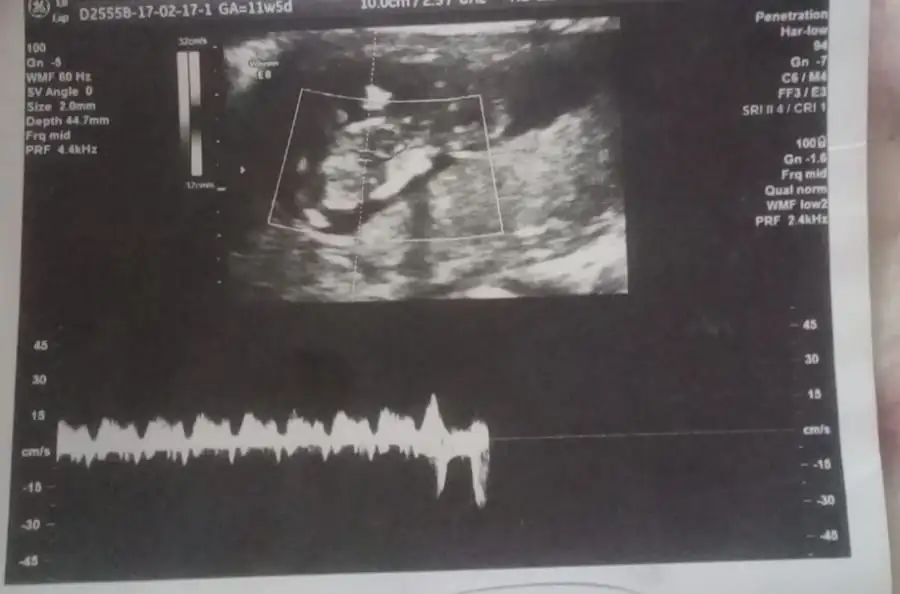

Amin canım inşallah 2-3 hafta sonra özele gidecem cinsiyeti belki der o zamanda ultrason resmi atarımCanım kesede yer ve yön olarak kız gibi geldi bana sadece kafası yuvarlak oluşu kafamı karıştırdı. Bazı resimlerde net yuzde 99 emin olabiliyorum. Senin bebeğine net birşey diyemiyorum canim. Inşallah hayırlı sağlıklı salih bir oğlun olur. Rabbim nasip etsin hepimize. Amin